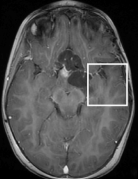

Note that term 2 is sparse if there are no major changes between and , both images have similar grey-level intensities and they are spatially matched. While these conditions meet in many application of dynamic imaging, such as prior image constrained compressed sensing (PICCS) in CT (Chen et al., 2008; Lauzier et al., 2012) and dynamic MRI (Jung et al., 2009; Lustig et al., 2006; Gamper et al., 2008; Yip et al., 2014), in longitudinal MRI none of these requirements are guaranteed. While there are solutions for miss-registration and variable grey level intensities (see Section 4), the temporal similarity in longitudinal MRI is a-priori unknown. Although longitudinal MRI may exhibit temporal similarity (Samsonov et al., 2010), we have to take into account that in many cases the follow-up scan may exhibit substantial changes with respect to the baseline scan. Such cases may occur, for example, if a surgical intervention was applied between the time points or if there is a major progressive or therapy response. Figure 2 shows two representative examples.

Baseline 4 months Baseline 3 months

Hydrocephalus GBM